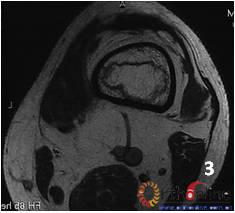

(三) 国内外的研究显示,在对股骨头坏死塌陷预测的方法中,以日本骨坏死研究会(Japanese investigation committee,JIC)依坏死部位对ONFH分型的准确性较高(图4)。本分型对JIC分型法进行改良,并对比。

图 4 日本骨坏死研究会依坏死部位分型

Fig 4 Japanese investigation committee (JIC) classification for ONFH